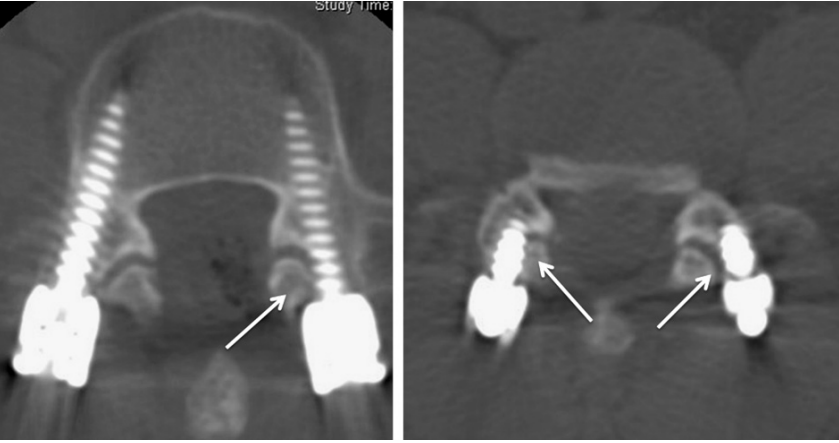

3.Park分级

1级:螺丝明显进入关节腔内

2级:螺帽明显进入关节腔内

3级:螺丝或螺帽进入关节腔内< 1 mm或邻接关节

4.Seo分级

0级:螺钉明显避开关节

1级:螺钉接触或疑似已侵入关节

2级:螺钉明显破坏关节